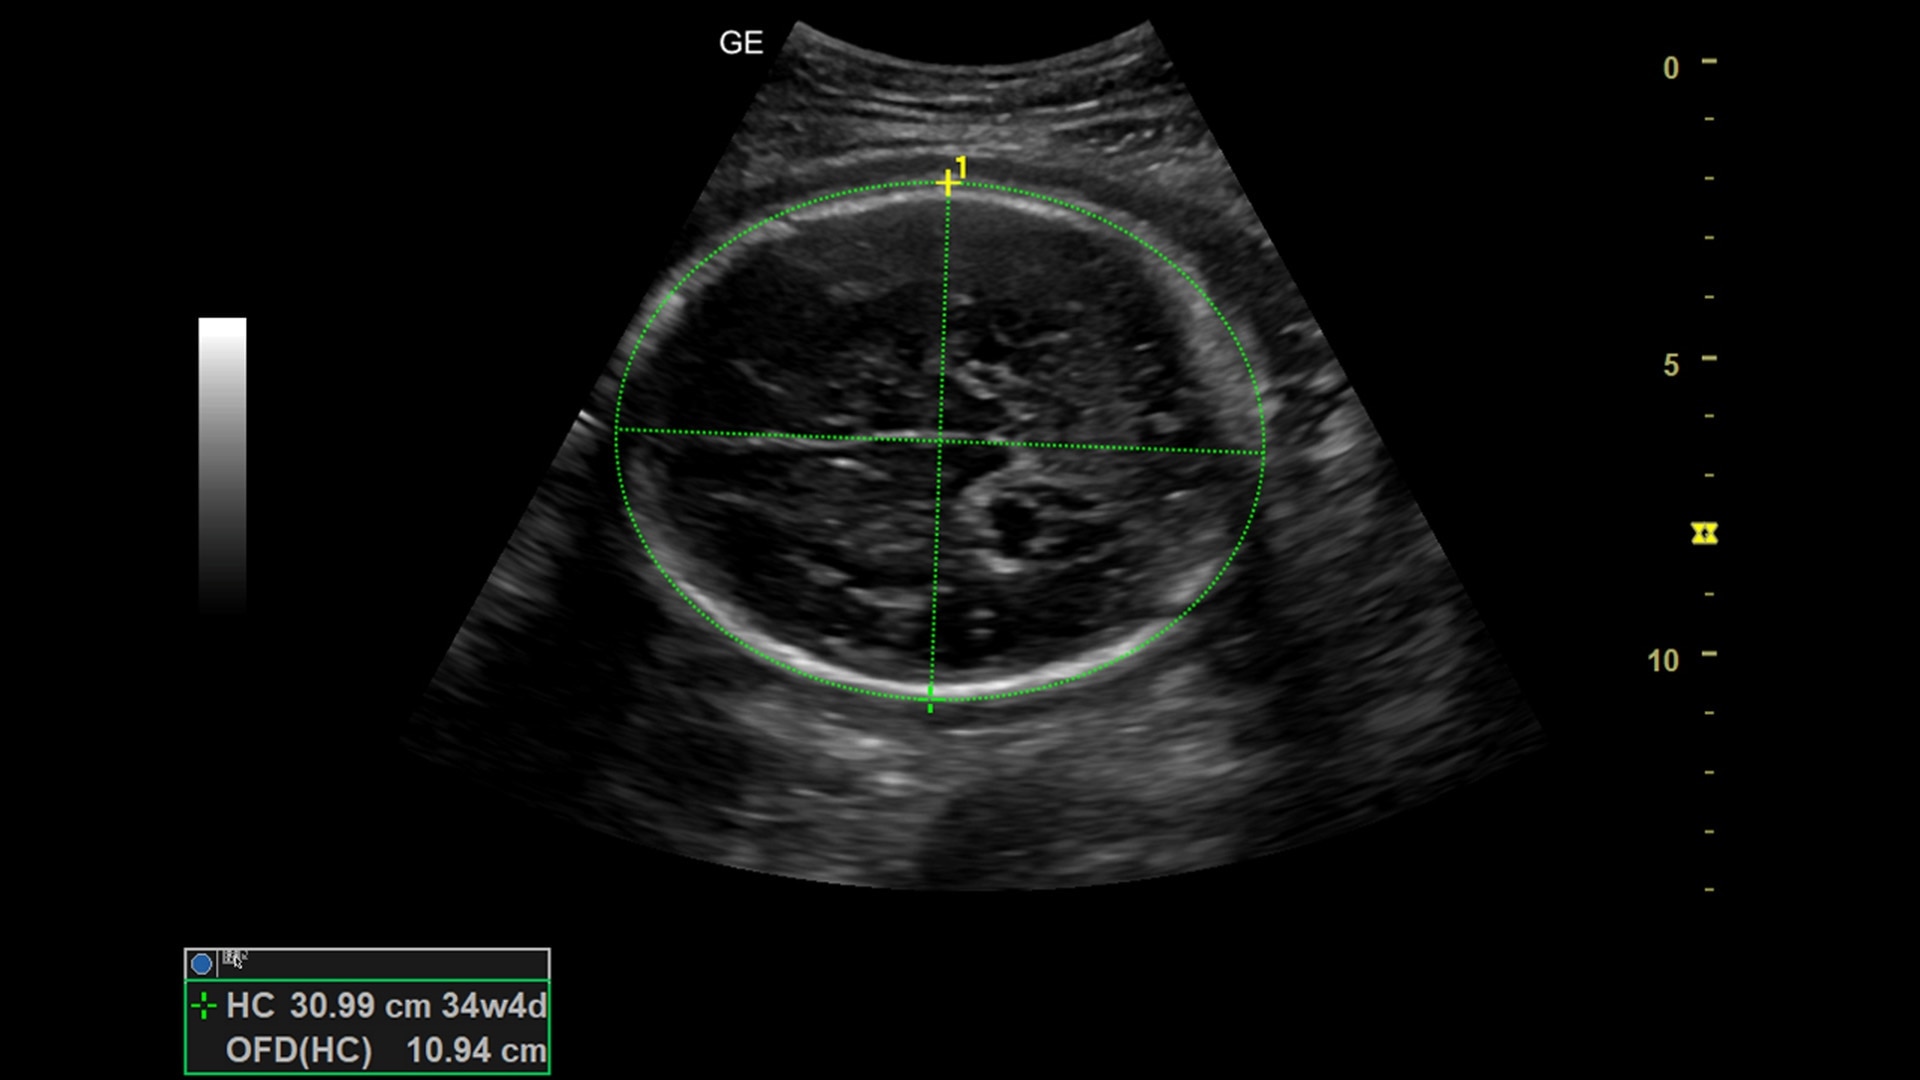

Practical

Perform a full range of exams and scans with a wide variety of probes